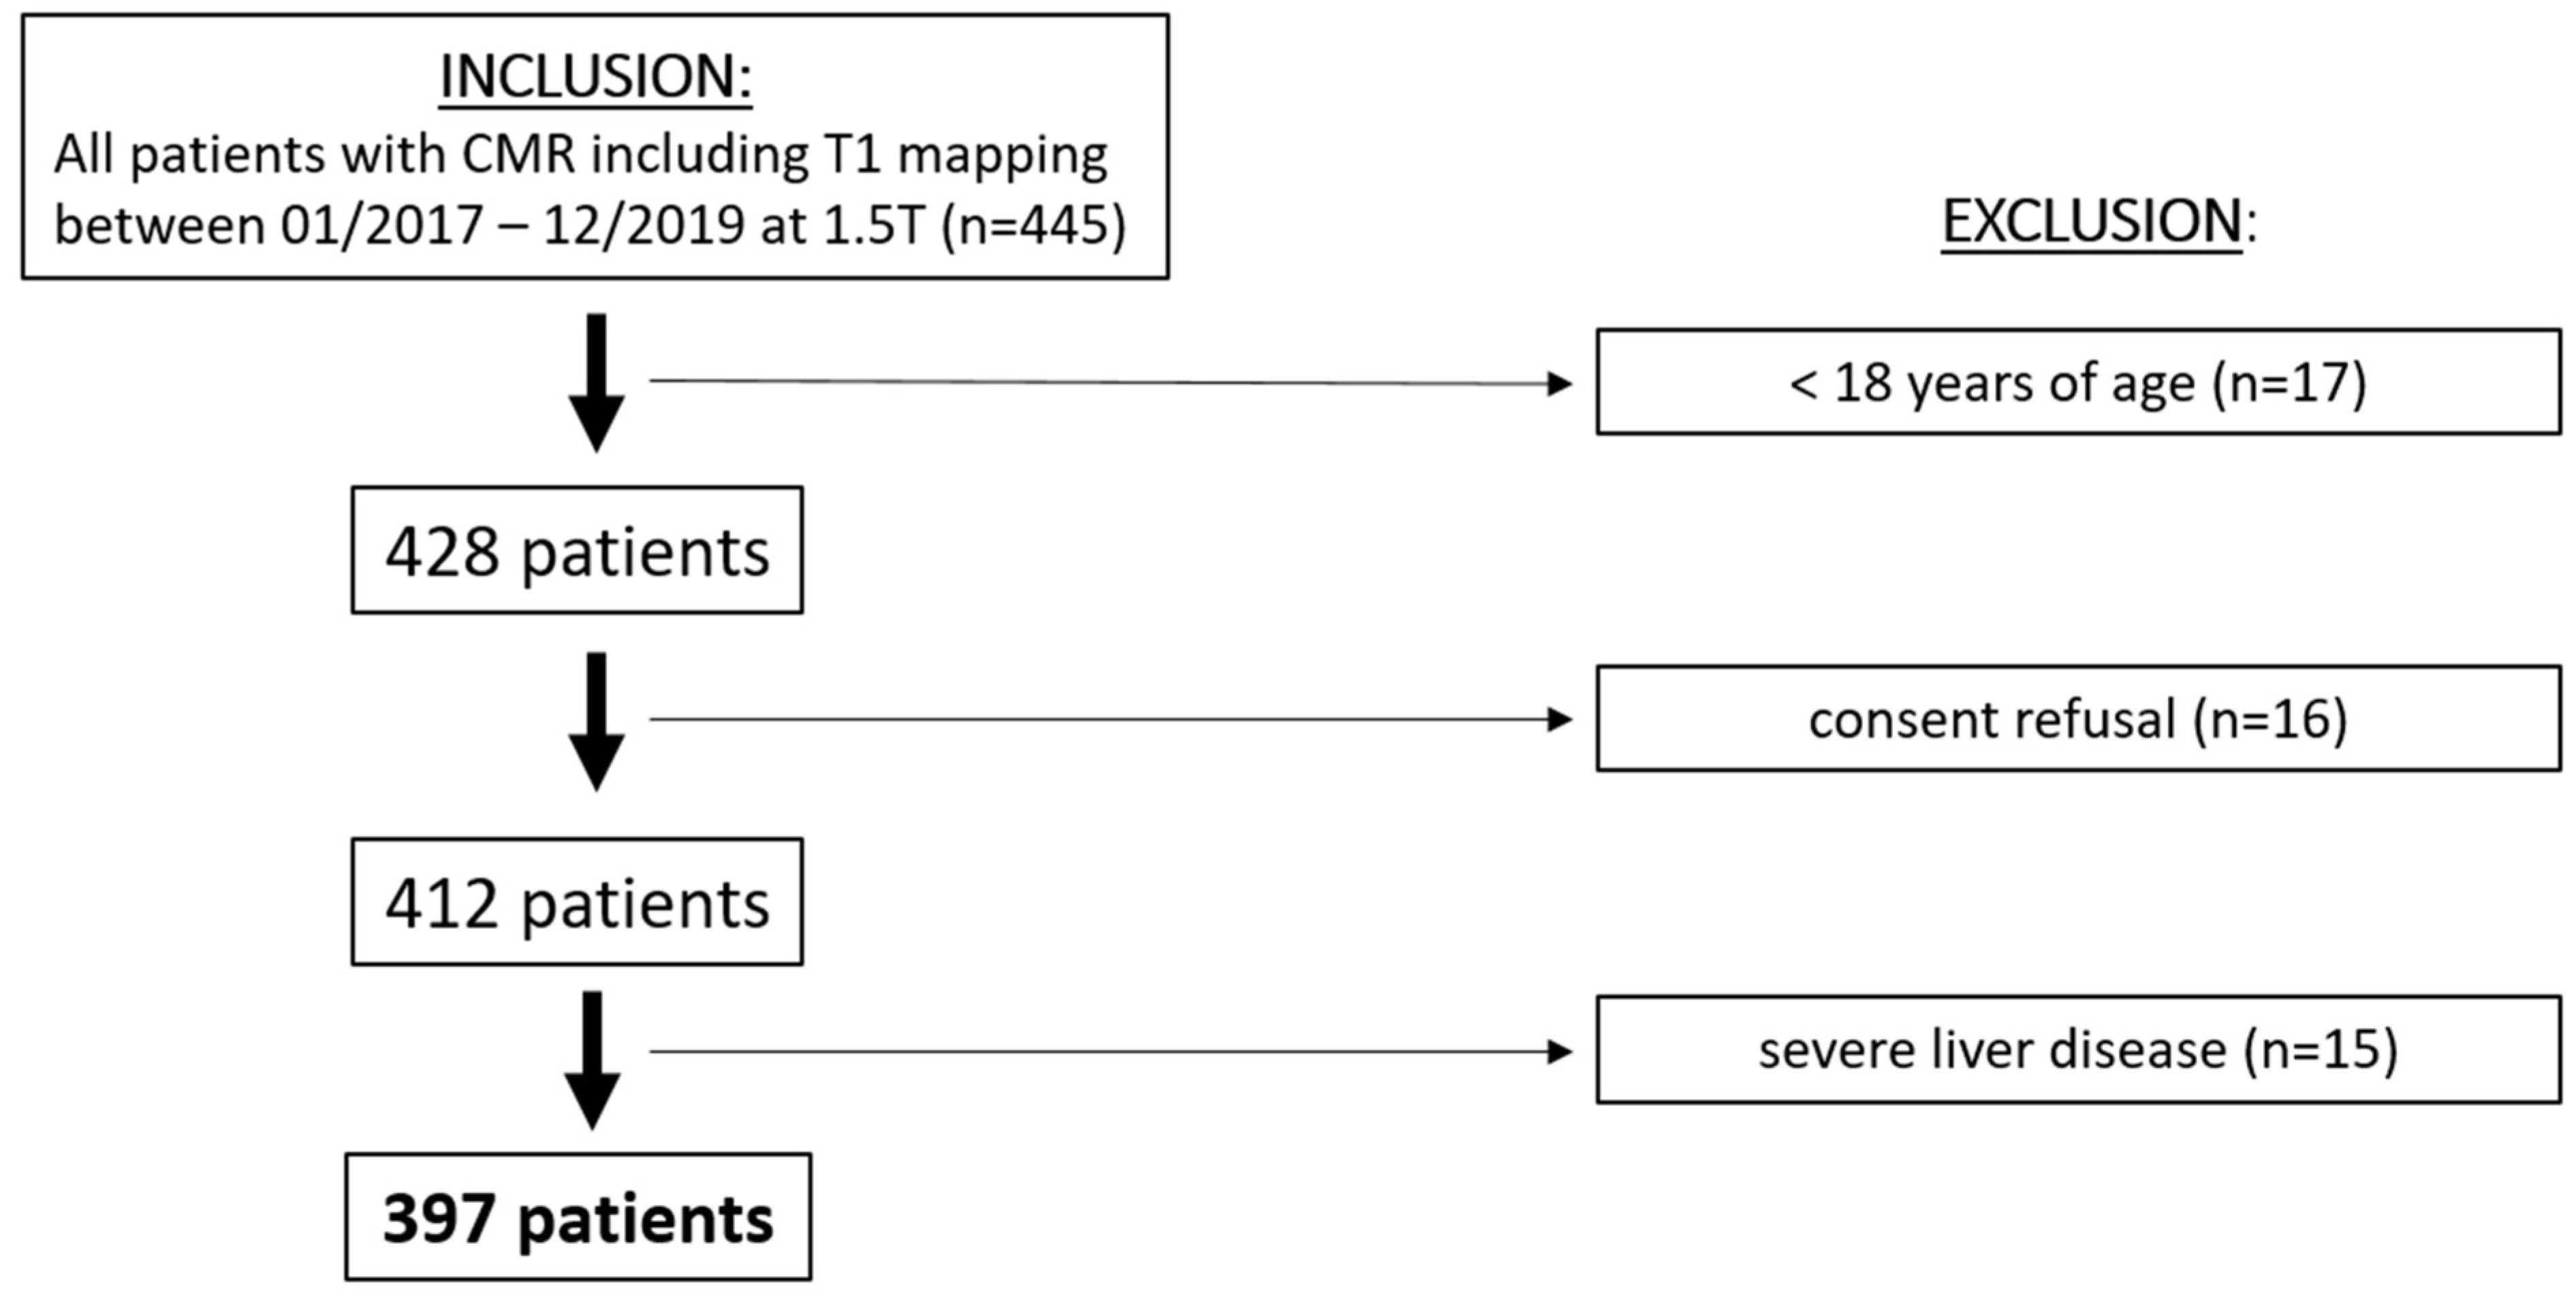

3.1. Final Study Population